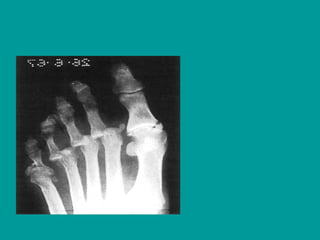

Central Metatarsal Fractures

• The second, third, and fourth metatarsals are

bound by several ligamentous attachments that

provide inherent stability to these bones.

Fractures of the central metatarsals are much

more common than the first metatarsal.

Fractures can occur in the shaft, head, neck, or

base. When diagnosing fractures of the base,

however, the emergency physician should

consider the possibility of instability within the

Lisfranc joint

Imaging

• AP, lateral, and oblique views are usually

adequate in demonstrating these fractures